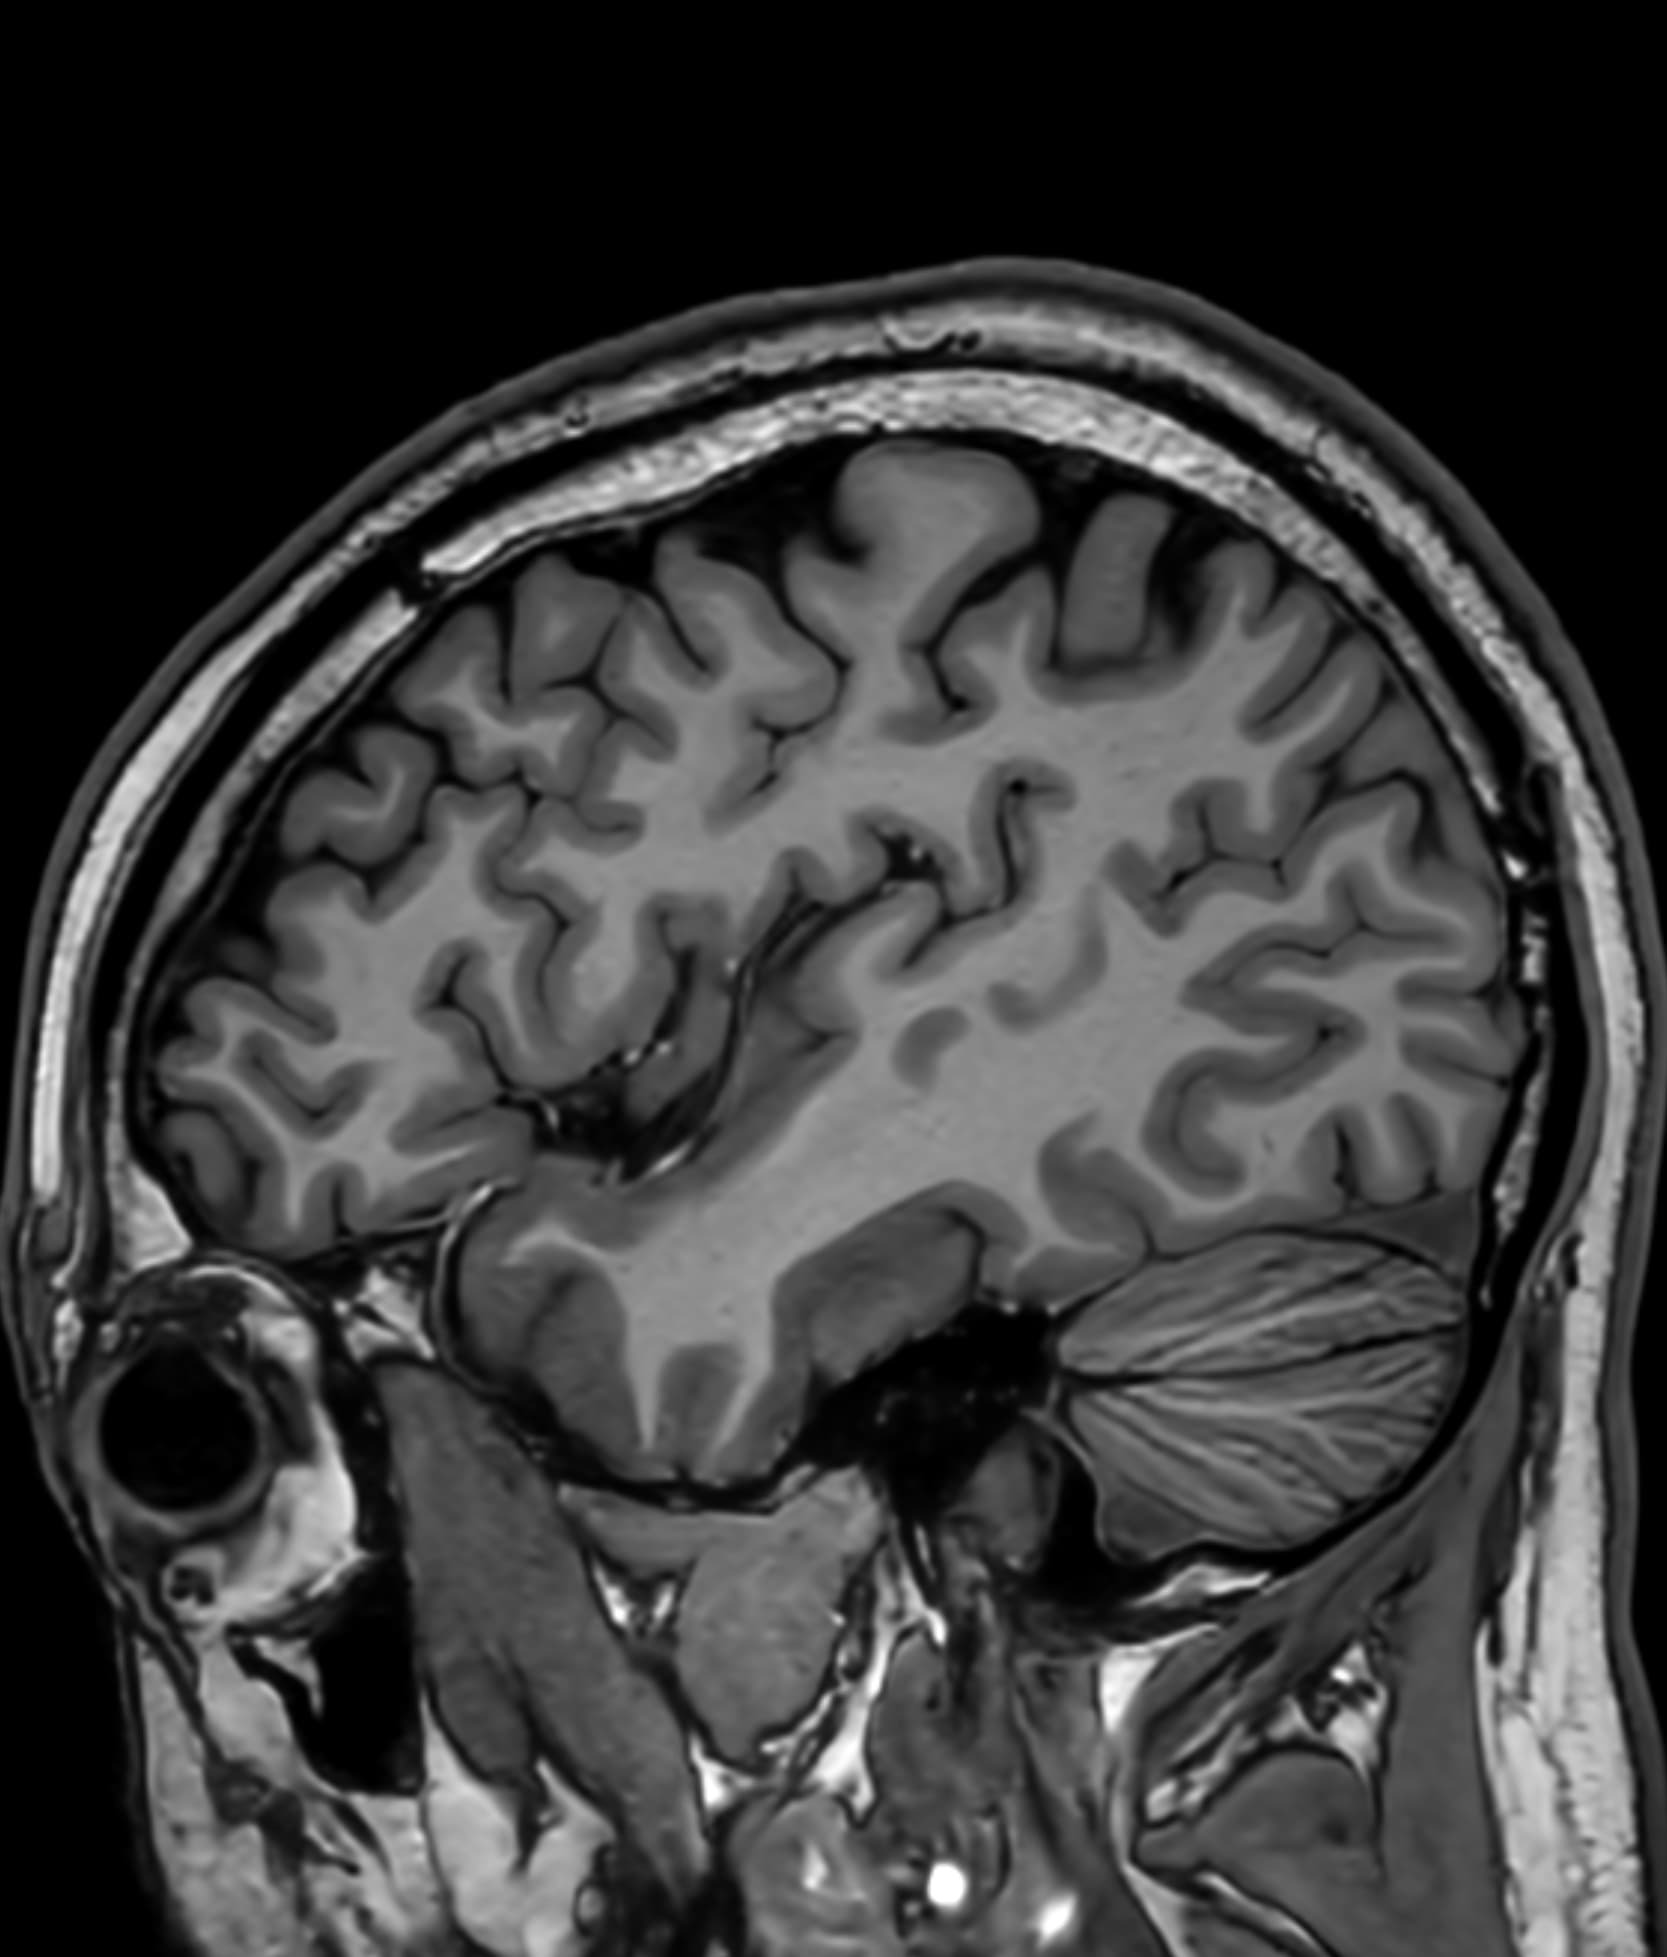

See real-world examples of SwiftMR™ across various MRI systems and anatomical regions

Scan time 03:14

Scan time 02:07